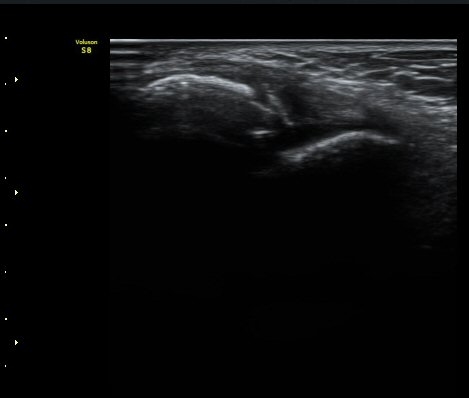

¹ß¸ñ°üÀý Á¾´Ü¸é°Ë»ç¿¡¼­ °üÀý³» ¼ö¾×Àú·ù°¡ °üÂûµÈ´Ù(±×¸² 1).

Àü°Å°ñºñ°ñÀδë Á¾´Ü¸é°Ë»ç»ó Àδë ÀδëÀÇ Àú¿¡ÄÚ ºÎÁ¾°ú ºñ°ñ

ºÎÂøºÎ ¹Ì¼¼ °ß¿­°ñÀýÀÌ °üÂûµÈ´Ù(±×¸² 3, 4).

ÃÊÀ½ÆÄÅõ½ÃÇÏ ºÎÇϰ˻翡¼­ ºñ°ñ°ú °ß¿­°ñÀý °ñÆí»çÀÌ¿Í ºñ°ñ°ú °Å°ñ »çÀ̰¡ ¹ú¾îÁø´Ù

(樨毢 1)